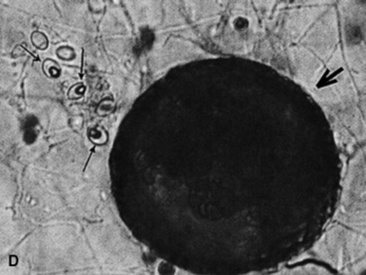

Cryptococcosis is caused by C. neoformans (var. neoformans and var. gattii) and is a ubiquitous, saprophytic, round, basidiomycetous yeastlike fungus with a large heteropolysaccharide capsule that does not take up common cytologic stains (see Table 31-5, Fig. 31-20). The capsule forms a clear halo when stained with India ink. The capsule is immunosuppressive and antiphagocytic. A relatively high frequency of equine cryptococcosis occurs in Western Australia.311 There is an epidemiologic relationship between C. neoformans var. gattii and the Australian river redgum tree (Eucalyptus camaldulensis), whereas C. neoformans var. neoformans has historically been associated with bird (particularly pigeon) excreta.311 Cytologic or histopathologic identification is very reliable for diagnosis because of the characteristic morphology.361 Serologic testing with latex agglutination to identify cryptococcal capsular antigen is useful with resolution of lesions correlated with declining serum titers.331

image

Fig. 31-20 Photomicrographs of an impression smear from a biopsy of a mass in the nasal passage of a horse. The smear is extremely cellular, with abundant neutrophils and macrophages. Round yeast cells with large nonstaining capsules and occasional narrow-based budding consistent with cryptococcal organisms (arrow) are shown. (Modified Wright stain ×100.)

Courtesy Elizabeth Welles, Auburn University, Auburn, Ala.